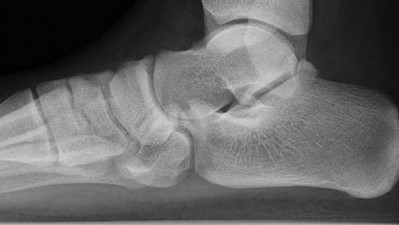

Figures 1a through 1c

Calcaneonavicular (CN) coalition

- Calcaneonavicular (CN) coalition**_

Figure 1a shows talar beaking (TB), an AE, and an open middle facet (MF). Figure 1b shows a wide navicular (WN), and Figure 1c shows an abnormal articulation between the calcaneus and the navicular, all consistent with a CN coalition.